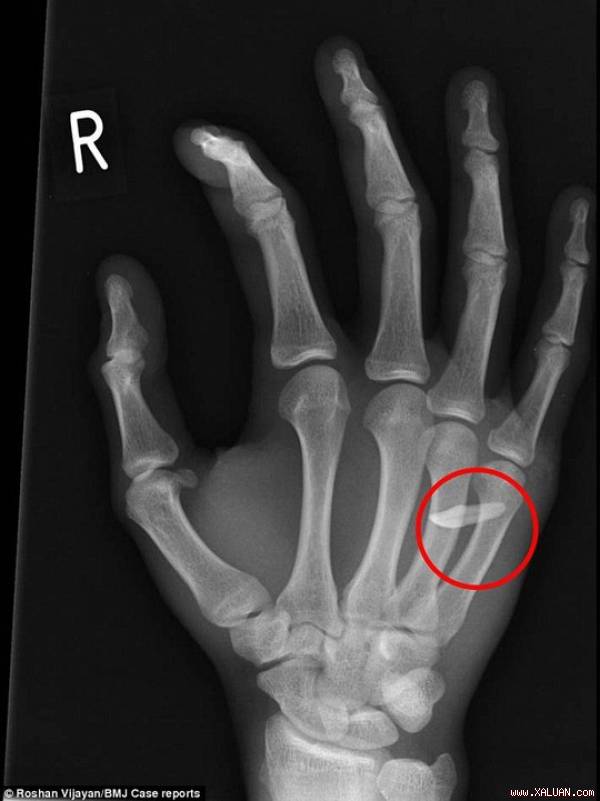

Hình chụp X-quang cho thấy răng cửa mắc trong đốt xương tay

Daily Mail ngày 6-5 đưa tin các bác sĩ ở Bệnh viện Nữ hoàng Victoria ở hạt West Sussex, Anh đã tiếp nhận một trường hợp bàn tay sưng to do một chiếc răng mắc kẹt giữa các khớp ngón tay mà nạn nhân không hay biết.

Nam thanh niên 19 tuổi kể rằng đêm trước đó, anh chàng đã dùng tay đấm vào miệng em trai mình nhưng không biết đối phương mất một chiếc răng.

Trường hợp này được đăng trên tạp chí BMJ Case Reports số ra mới nhất. Thanh niên cho biết sau khi phát hiện tay mình chảy máu, anh ta liền rửa dưới vòi nước. Tuy nhiên, ngày hôm sau, anh ta thức dậy trong đau đớn, cả bàn tay sưng tấy, các ngón tay hầu như không cử động được. Ngay lập tức, anh chàng vội vã đến phòng cấp cứu Bệnh viện Nữ hoàng Victoria để tiêm phòng uốn ván, điều trị kháng sinh và làm sạch vết thương bằng nước muối.

Đội phẫu thuật thẩm mỹ ngay lập tức được gọi tới và các bác sĩ chẩn đoán anh có vết cắn nhiễm trùng, lập tức cho chụp X-quang bàn tay. Kết quả X-quang đã khiến nam thanh niên vô cùng ngạc nhiên khi một chiếc răng cửa mắc kẹt trong bàn tay. Các mẫu gạc cho thấy vết thương chứa rất nhiều vi khuẩn. Ngay lập tức, thanh niên được đưa lên bàn mổ, gây mê tổng quát và gắp bỏ chiếc răng tai hại.

Sau 2 ngày nằm viện, bệnh nhân đã xuất viện và cơ thể phục hồi rất tốt. Viết trên tạp chí, tiến sĩ Roshan Vijayan – một bác sĩ phẫu thuật tại Bệnh viện Nữ hoàng Victora – cho biết ca bệnh cho thấy tầm quan trọng việc tìm hiểu bệnh án và chụp X-quang.

“Trường hợp này không bình thường ở chỗ toàn bộ chiếc răng đã cắm vào tay bệnh nhân không để lại dấu vết, trong khi bệnh nhân không hề biết về điều này” – vị bác sĩ nói.